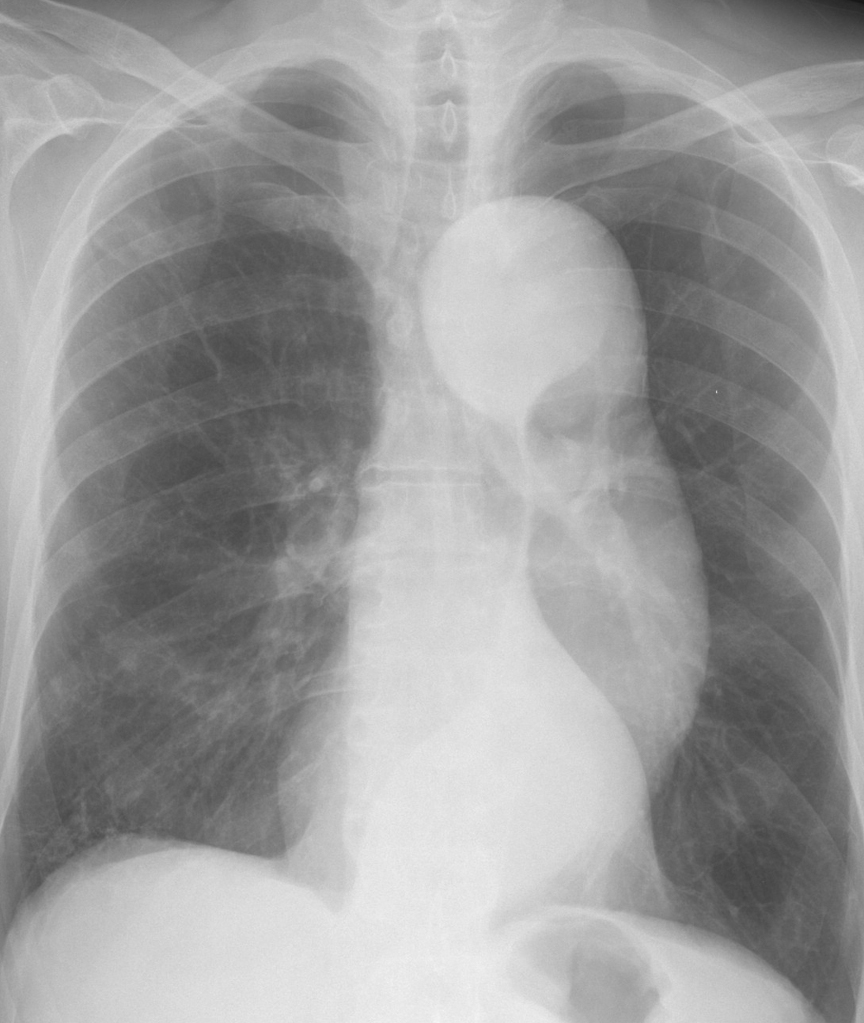

Aorta

Aneurysm

Ao Aneurysm 4a